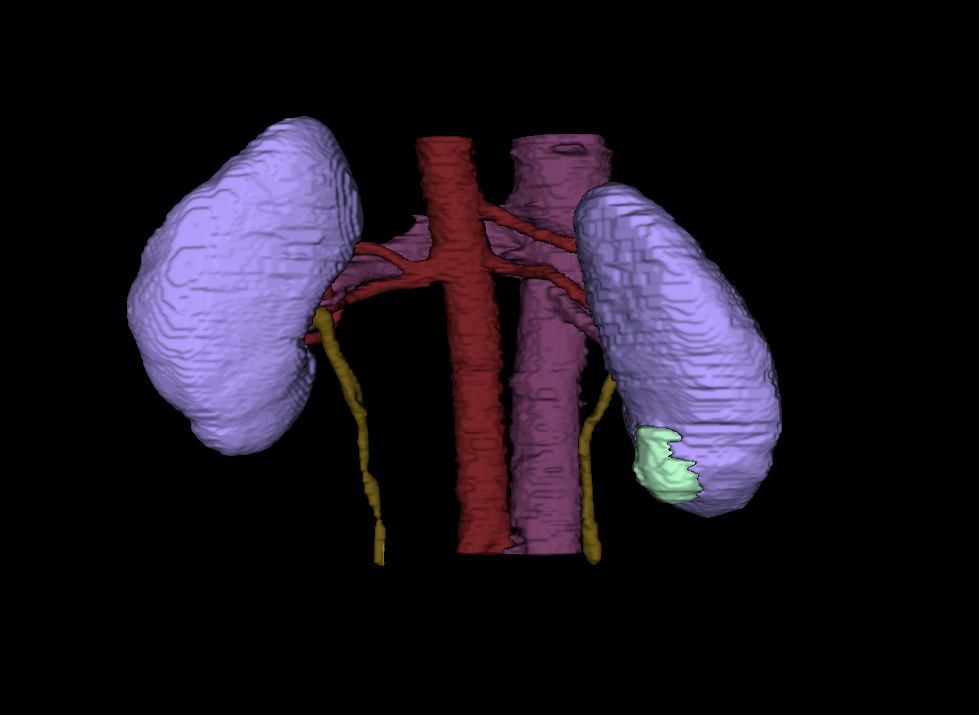

With a click of a button, ARCS Scholar Nick Heller is helping radiologists identify and analyze kidney tumors within a patient’s body.

Heller is a PhD student conducting computer science research at University of Minnesota. His research focuses on using computer technology to enhance medical imaging, like a CT scan or an MRI. According to Heller, the magnified images will allow radiologists to quantify the type of tumor it is, saving time between a patient’s diagnoses and treatment.

“They will be able to measure a tumor mass, determine how big and rough they are, and whether they look distinct or blurry against the background. Medical professionals can use that information to choose the most effective treatment and predict a patient's outcome,” Heller explains.

The ARCS Scholar compiles information from the medical charts of real patients. He and other team members also work with radiologists to create hypothesis about how the appearance of a kidney tumor will relate to that patient’s outcome. Heller assigns numbers to each distinct feature the tumor. For instance, if a radiologist determines a tumor has a “hard boundary,” then Heller would quantify that description as anything over the number sixty.

“Then we can turn those numbers into a computer code. If we can automate the code with images and equipment, a radiologist can just hit a button and receive information on the tumor, rather than looking at the image and making a judgement call,” Heller states.